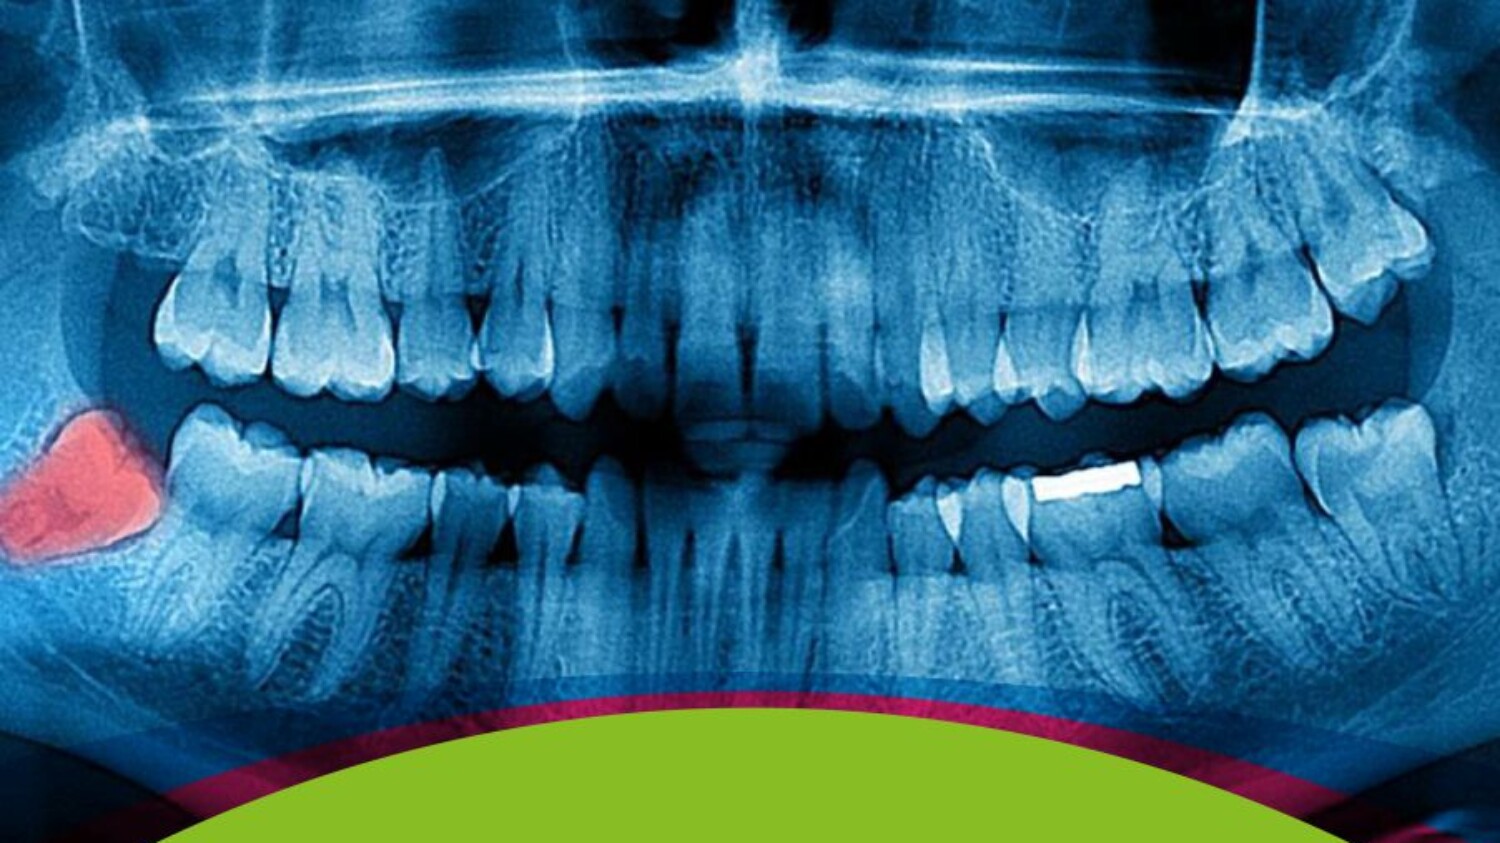

- Impactación: Cuando la muela del juicio queda atrapada bajo la encía, o crece solo parcialmente, o contra otro diente.

- Malposición: La muela crece en una dirección incorrecta, empujando contra otros dientes.

- Quistes o daños en el hueso: En casos más graves, pueden formarse quistes alrededor de una muela del juicio impactada, lo que podría dañar la estructura ósea.